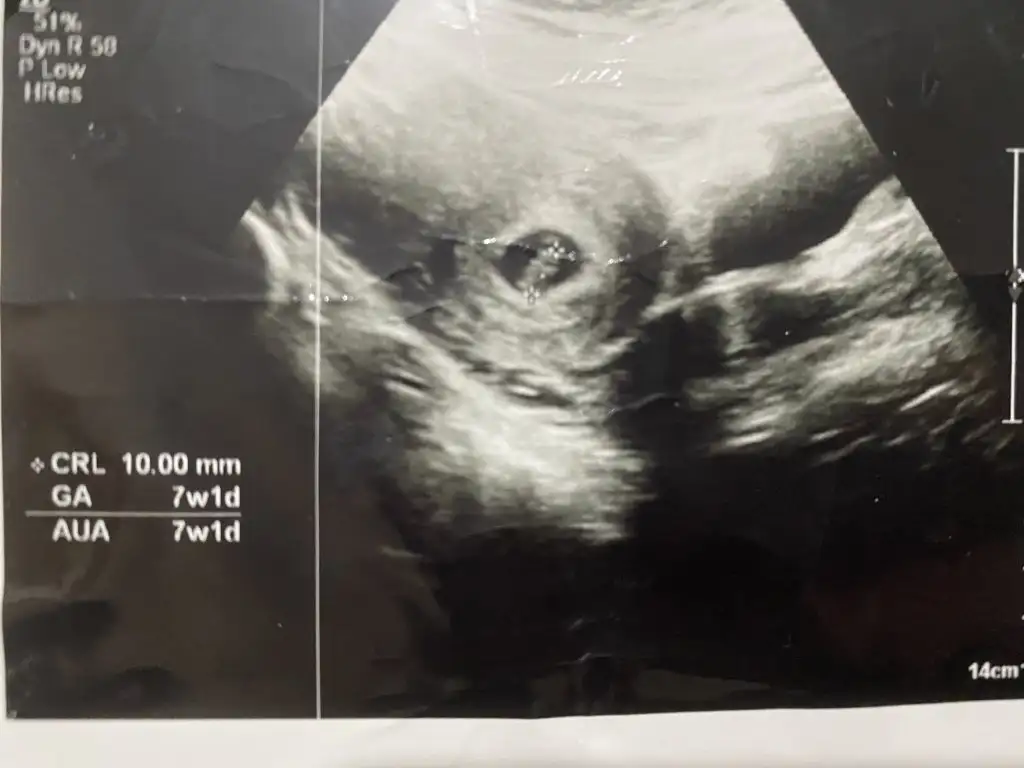

8+3 günlük tahminde bulunur musun canımvallahi atlamışımsenin prenses gibi canım öğrenince haberlerini bekliyorum